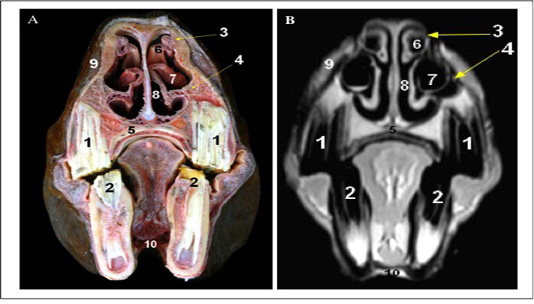

Cross sectional anatomy (Panel A) and MR image (Panel B) of horse head at the level of the third premolar tooth. 1) Upper third premolar tooth; 2) Lower third premolar tooth; 3) Dorsal turbinate crest of Nasal bone; 4) Ventral turbinate crest of maxilla bone; 5) Palatine process of Maxilla; 6) Dorsal nasal concha; 7) Ventral nasal concha (bulla); 8) Common nasal meatus; 9) Superior labii levator muscle; 10) Geniohyoid muscle.